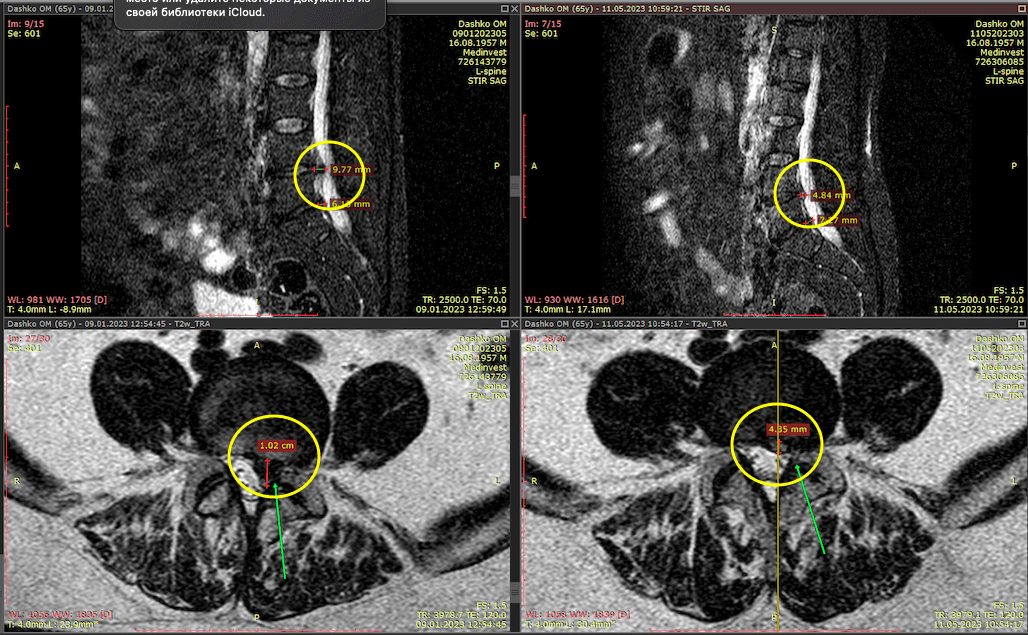

Метод лікування грижі шляхом стимуляції резорбції в Україні був впроваджений у 2020-2021 роках.  Алгоритм оцінки грижі на предмет резорбції, що використовується у клініках – є авторським, розроблений лікарем Боханом А.Ю.